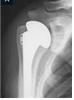

| 한글기술명 | 고관절치환술 | 영문기술명 | Hip Replacement Artroplasty |

| 세부기술 | ▪ 고관절 반치환술, 전치환술 | ||

| 정의 및 특징 | 인공고관절치환술이란 인체의 고관절이 질병이나 외상으로 인하여 관절이 파괴되어 동통을 유발하고 정상적인 기능을 하지 못할 때 인공고관절로 부분 혹은 전체를 치환함으로써 동통을 감소 혹은 제거하고 관절의 기능을 보존하는 매우 성공적인 치료 방법이다. 인공고관절 전치환술은 골반의 비구 및 대퇴골두를 모두 치환하는 수술이고 인공고관절 반치환술은 비구부는 치환하지않고 대퇴골두만 치환하는 술식을 말한다. | ||

| 시술방법 | 고관절을 전방, 혹은 측방, 혹은 후방 도달법으로 도달하여 고관절을 노출시킨 후 비구부 확공기로 비구 연골을 제거하여 연골하골을 노출시키고 비구컵을 삽입하고 금속 나사로 비구컵을 골반골에 단단히 고정한다. 그 후 비구컵 내에 세라믹 혹은 금속 혹은 프라스틱 라이너를 비구컵 안쪽에 삽입한다. 그 후 대퇴경부에서 절골술을 시행하여 대퇴경부를 제거하고 근위 대퇴골 골수강을 rasping 한 후 적절한 크기의 대퇴 스템을 단단히 삽입하고 인공 골두를 대퇴스템 경부에 연결시켜 비구컵의 라이너 안으로 고관절을 정복한 후 근육 및 근막, 피부를 봉합한다. | ||

| 경과(치료기간) | 대개 수술 후 1일째부터 침상에 걸터앉아 다리를 펴는 대퇴직근 수축 운동을 시작하고 2일째부터는 서는 연습을 시작, 잘 서게 되면 목발 보행을 시작하고 술 후 약 4-7일 째 퇴원하게 되며 환자의 상태에 따라 목발은 술 후 약 1-2 개월간 사용한다. | ||

| 우수성 | 인공고관절치환술은 인류가 개발한 치료 방법 중 가장 우수한 치료 방법의 하나이며 비용 가치 효용성이 가장 뛰어난 수술이다. 최근에는 잘 닳지 않는 관절면이 개발되어 사용되므로 평균 수명이 15년-20년 이상을 기대할 수 있게 되었다. | ||